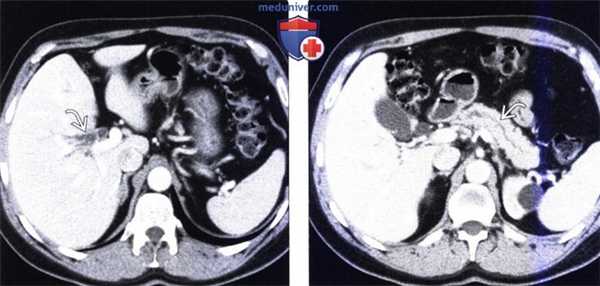

(Слева) На аксиальной КТ с контрастным усилением, выполненной мужчине 49 лет с жалоба -ми на боль в животе и нарушением функции печени, определяется расширение внутрипеченочных желчных протоков.

(Справа) На аксиальной КТ с контрастом определяется также расширение панкреатического протока. Эти изменения позволяют предположить злокачественное новообразование, расположенное в Фатеровой ампуле или возле ее, которое и послужило причиной обструкции.2. Рентгеноскопия при раке двенадцатиперстной кишки: